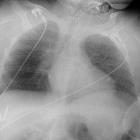

Zwerchfellschrittmacher

/ N. phrenicus - Stimulator im Röntgenbild. Röntgendichte Sondenspitzen am N. phrenicus beidseits auf den Herzrand projiziert.